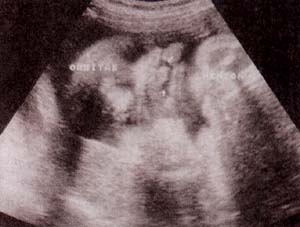

fig. 62. – (a). 18 semanas.corte sagital. |

fig. 62. – (b). corte transversal. estas formas de inicio precoz se hallan con frecuencia asociadas a anomalías cromosómicas. |